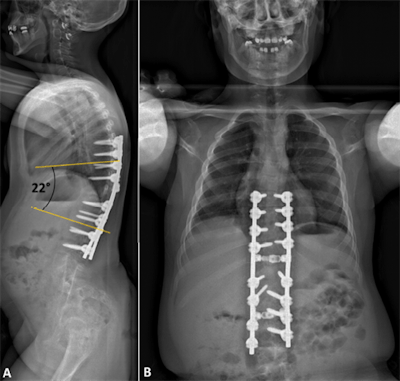

With the 3D-printed spine and guiding templates at hand, the surgical team was able to successfully resect the spinal deformity and close the separation. The young patient left the hospital eight days after surgery without any neurological deficit. Postoperative x-rays demonstrated the surgeons had properly corrected her spinal deformity.